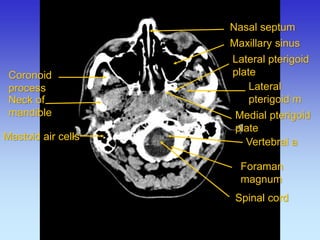

Coronoid process

Neck of mandible

Lateral pterigoid m

Lateral pterigoid plate

Medial pterigoid plate

Maxillary sinus

Nasal septum

Mastoid air cells

Styloid process

Spinal card

Foraman magnum

Vertebral a

Spinal cord